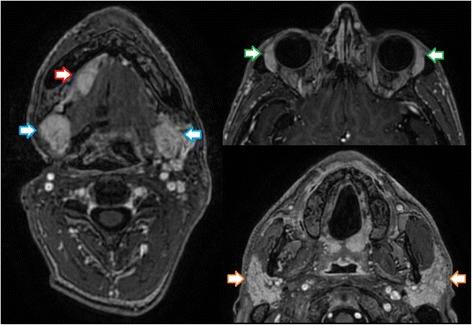

Patient was first diagnosed with locoregionally advanced, non-keratinizing nasopharyngeal carcinoma in 2010. After achieving complete remission following induction chemotherapy and concurrent curative chemoradiation, the patient subsequently developed distant and locoregionally recurrent disease. He received various treatments (neck dissection, radiotherapy to a bony metastasis, palliative chemotherapy, stereotactic re-irradiation of local recurrence) before initiation of anti- PD-1 immunotherapy with pembrolizumab in January of 2016. Following marked local progression 6 months thereafter, we performed re-re-irradiation of the recurrent tumor after careful evaluation and treatment planning. While treatment was well tolerated, the patient subsequently developed marked clinical and radiological signs of immunostimulation with mucosal irritation and swelling of lacrimal and salivary glands as described in the report. Immunotherapy with pembrolizumab was reinitiated, with re- staging showing excellent response with regression of all tumorous lesions. At the time of this report, following near complete recovery of inflammatory symptoms, the patient remains in excellent condition and free from recurrence under treatment with pembrolizumab.

患者于 2010 年首次诊断为局部晚期、非角化性鼻咽癌。在诱导化疗和同期根治性放化疗后达到完全缓解后,患者随后出现远处和局部复发疾病。在 2016 年 1 月开始接受抗 PD-1 免疫疗法帕博利珠单抗治疗之前,他接受了各种治疗(颈部清扫术、骨转移放疗、姑息性化疗、局部复发立体定向再放疗)。6 个月后局部进展明显,我们在仔细评估和治疗计划后对复发性肿瘤进行了再放疗。虽然治疗耐受性良好,但随后患者出现明显的免疫刺激临床和影像学迹象,如报告所述的黏膜刺激和泪腺及唾液腺肿胀。重新开始使用帕博利珠单抗免疫治疗,重新分期显示所有肿瘤病变均有极好的反应,完全消退。在本报告时,在炎症症状几乎完全恢复后,患者在帕博利珠单抗治疗下状况良好,无复发。